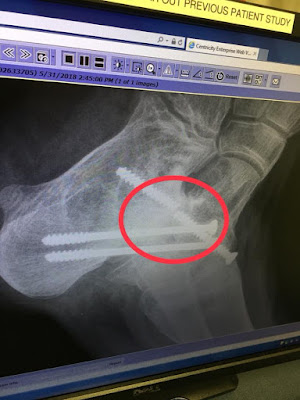

Now for what HAD to be done�The left foot went as expected

and even a little better than expected.�

The surgeon was able to get the entire broken screw out of his foot

without damage.� That was huge, because

he really thought he would have to leave the back half of the screw in.� He used the bone harvested from Parker�s hip

to repair the left subtalar fusion and added a new titanium screw.� Then, he went into the right foot and

unfortunately there was a screw loose in addition to the cadaver bone

failing.� So the loose screw was pulled

out and he reinforced the bone with the harvested hip bone and put in a smaller

screw to fuse the foot again.� The left

foot/ankle is casted and the right foot is splinted.� Both feet/legs are numb from the epidural,